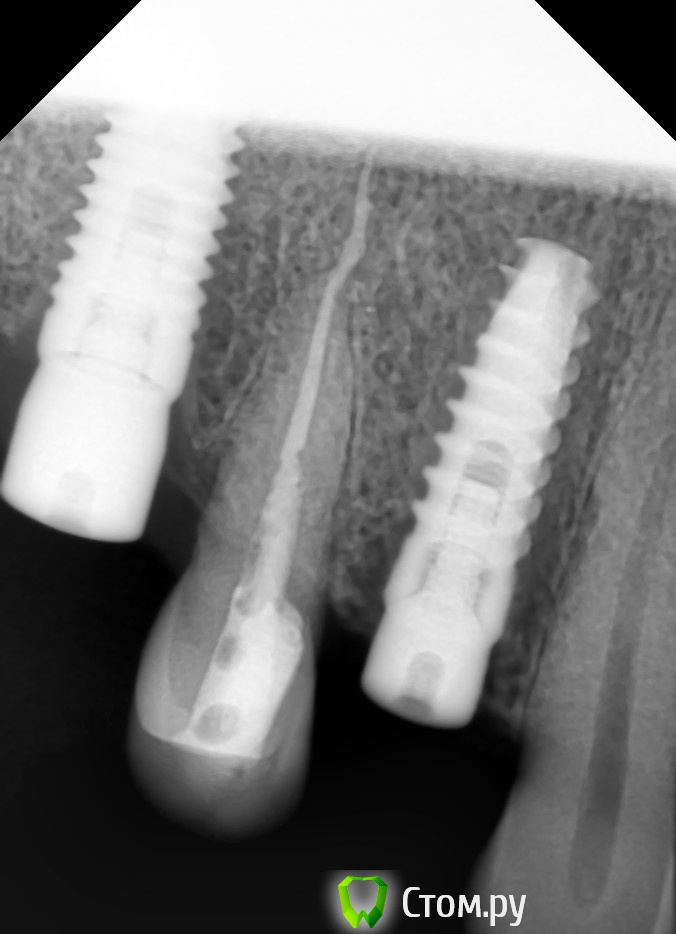

Большой Зеленый Опубликовано 23 ноября, 2013 Автор Поделиться Опубликовано 23 ноября, 2013 http://i016.radikal.ru/1504/ae/1eb7db3d9bc5.jpg вроде не критично ) Ссылка на комментарий

pit Опубликовано 23 ноября, 2013 Поделиться Опубликовано 23 ноября, 2013 вроде не критично )Да вообще норм. Но в 3-м секторе дистальный наклон имеется. Ссылка на комментарий

pawa Опубликовано 23 ноября, 2013 Поделиться Опубликовано 23 ноября, 2013 46,47 шейки имплантатов не в кости? Ссылка на комментарий

Большой Зеленый Опубликовано 23 ноября, 2013 Автор Поделиться Опубликовано 23 ноября, 2013 46,47 шейки имплантатов не в кости?В кости. Ссылка на комментарий